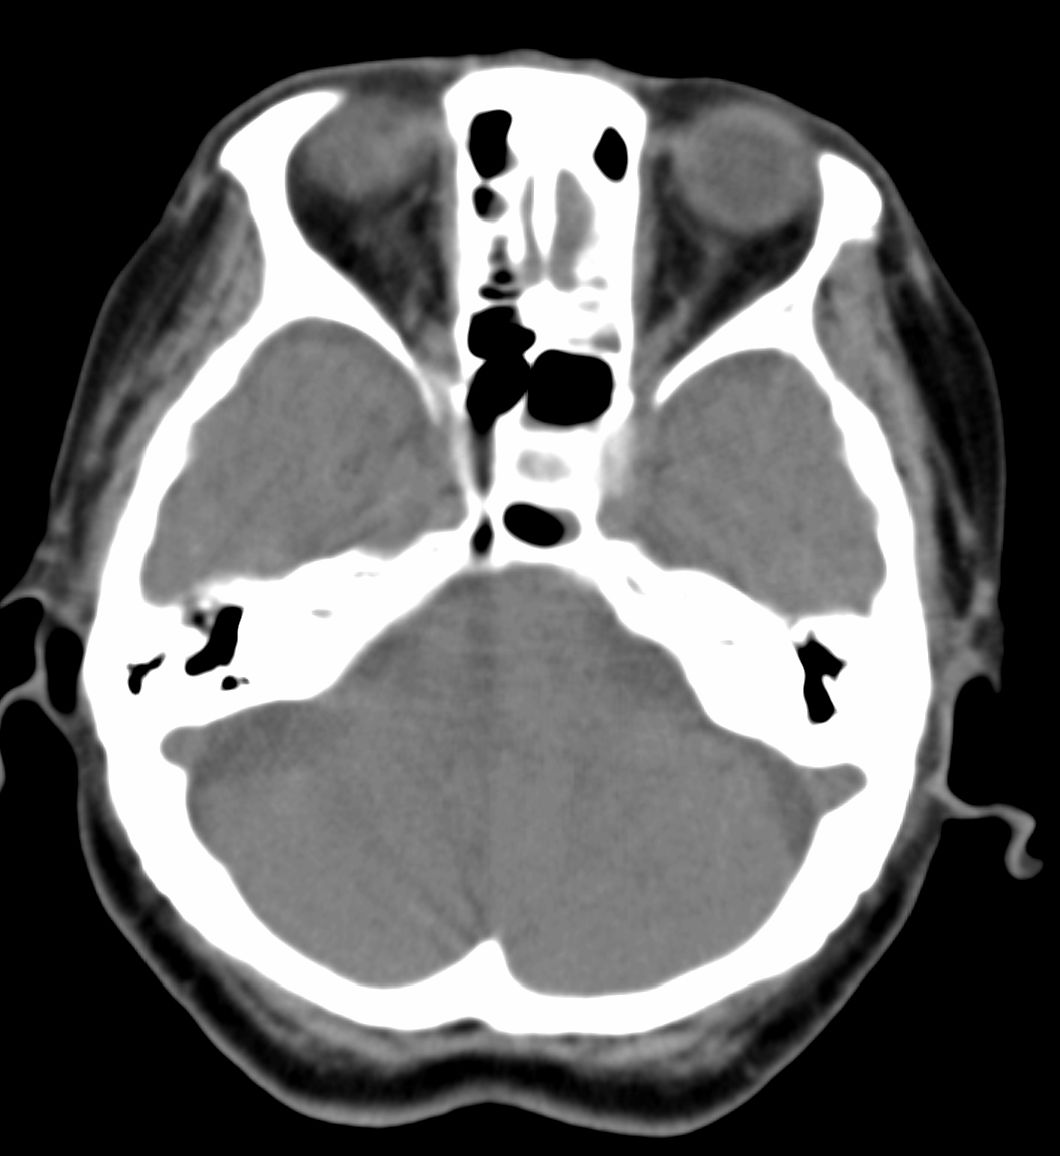

女,69岁。鼻出血2月多。(会诊病史就这样简单)鼻副窦ct检查如下:

左侧鼻腔及上颌窦见软组织块影,左侧上颌窦腔扩大,骨质吸收,右侧上颌窦见半圆形软组织密度影,鼻中隔向右侧弯曲,左侧鼻和鼻窦内翻型乳头状瘤可能性大,建议增强。

左侧上颌窦及鼻腔内见软组织密度影,其内密度不均匀,见斑片状高密度影,右侧上颌窦腔明显扩大,窦壁吸收变薄,鼻中隔右偏,右侧上颌窦见一半圆形软组织密度影,边界清楚,其内密度均匀。诊断,1、左侧鼻腔及上颌窦内翻乳头状瘤可能性大,上颌窦癌,息肉及霉菌性上颌窦炎待除外。2、右侧上颌窦粘膜下囊肿。

1)考虑左侧上颌窦内翻乳突状瘤突入左侧鼻腔。2)副鼻窦炎,右侧上颌窦黏膜下囊肿。

病理:霉菌性左侧上颌窦炎伴左侧上颌窦纤维组织增生。

窦腔密度不均匀增高,无明显钙化征象,后外侧及内侧窦壁膨胀明显,局部破坏消失,筛窦受累及,但双侧对比发现左侧窦壁骨质有硬化增白现象,这可能是支持左侧霉菌性上颌窦炎的主要依据点。